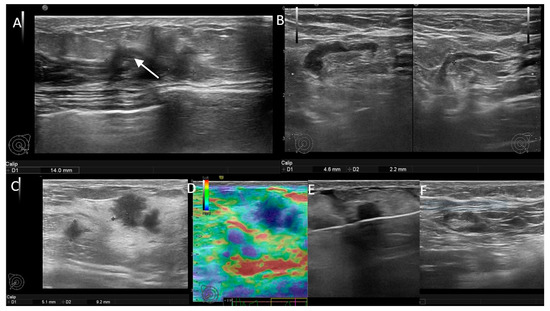

Figure 2. (A,B) Patient with negative genetic testin-unifocal BIRADS 5 mass and positive axillary US. There is an ipsilateral lymph node with cortical thickness up to 4.4 mm (white arrow), compared to the contralateral node, which has only 2.2 cortical thickness. (CF) Patient with BRCA2 mutation-bifocal BIRADS 5 masses and negative axillary US. There is an ipsilateral node with fatty hilum and a thin cortex of 2 mm.

Figure 3. (AD) Patient with negative genetic testing and positive axillary US. There is a lymph node with focal cortical thickening (white arrow), increased vascularity and stiff strain elastography appearance. (EG) Patient with CHEK2 mutation and positive axillary US. There are multiple, irregular lymph nodes, with eccentric hilum (white arrow), thickened cortex with punctate microcalcs (yellow arrow) and chaotic, periphery vascularity.